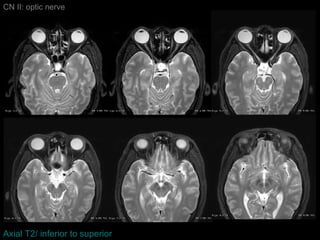

CN II: optic nerve Axial T2/ inferior to superior

CN II: opticnerve Axial T2/ inferior to superior